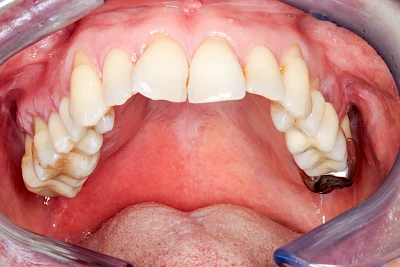

Diese Vermehrung von Bindegewebe in einem frei gewordenen Raum ist eine Sonderform der Anpassungsreaktion menschlicher Zellen und wird als Vakatwucherung bezeichnet.

Früher wurden im Unterkiefer mitunter Brücken zum Ersatz fehlender Zähne als sogenannte "Schwebebrücken" gestaltet. Die Idee dabei war, dass man die Brücke insgesamt besser reinigen kann. Allerdings war das für die Patienten mitunter irritierend für die Zunge und vor allem beim Essen gewöhnungsbedürftig. Teilweise haben sich hier reaktiv Vakatwucherungen der Kieferkammschleimhaut gebildet und den Raum unter der Brücke wieder verschlossen.